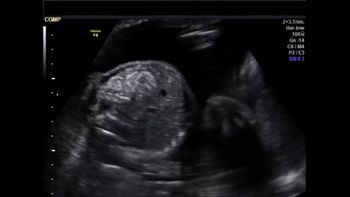

This 18-week fetus has a vascular anomaly. Can you identify it?